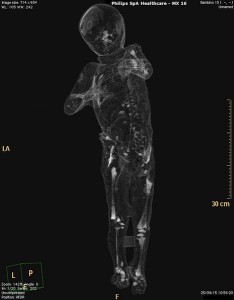

Al Santobono da Gaza per ricevere cure